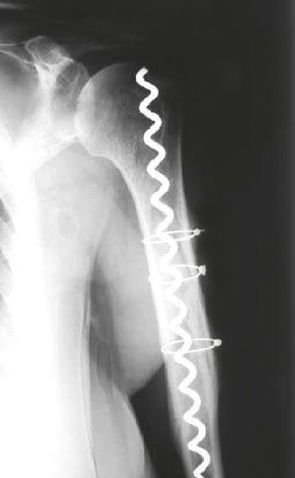

Long spiral fracture A1 with fissure extensions into the head in a 56-year-old woman. First of all rope cerclage via minimal intervention to restore the anatomy as a prerequisite for effective insertion of the BONEHELIX® in the same session. Rapid healing, free function.